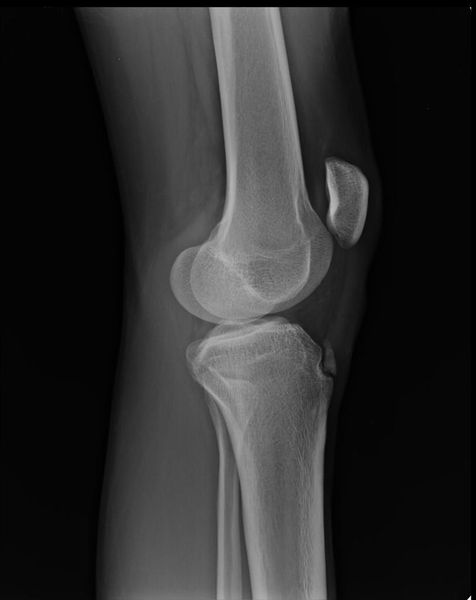

Основным методом инструментальной диагностики является рентген коленных суставов в двух проекциях, который позволяет увидеть структурные изменения бугристости [4] .

Фрагментацию с отрывом костного фрагмента лучше всего видно на боковой рентгенограмме [10] .

Рентгенологически отмечается характерная картина для этого заболевания. У молодых людей, когда еще не закрылась зона роста, видны неслившийся апофиз бугристости и отдельные костные фрагменты. Часто можно видеть значительную деформацию бугристости в виде «хобота». У более старших танцовщиков эта бугристость может иметь вид отдельных костных фрагментов.

Диагностика деформирующегося артроза коленного сустава несложна. Многие авторы выделяют триаду основных рентгенологических признаков, которым сопутствует соответствующая клиническая картина: неравномерное сужение суставной щели, склероз (уплотнение) субхондральных пластинок, краевые костные разрастания в области эпифизов костей и заострение межмыщелковых возвышений.

II степень - клинически определяется деформация коленного сустава, периодически возникает синовит, боль по суставной щели, пальпируются костные образования по суставным поверхностям, хромота возникает после физической нагрузки или при длительной ходьбе. Рентгенологически определяется сужение суставной щели, склероз субхондральных пластинок, заострение межмыщелковых возвышений и значительные костные разрастания. У артистов балета костные разрастания раньше возникают на надколеннике.

III степень — самая тяжелая степень развития деформирующего артроза. Клинически отмечается ограничение подвижности в коленном суставе, боли как после физической нагрузки, так и в покое, деформация сустава, выраженный хруст. В этой стадии синовиты бывают уже реже и сустав почти «сухой». Отмечается атрофия мышц бедра. На рентгенограмме суставная щель узкая, массивные костные разрастания, дегенеративные кисты в субхондральной зоне, суставные поверхности резко деформированы, явления подвывиха в суставе.